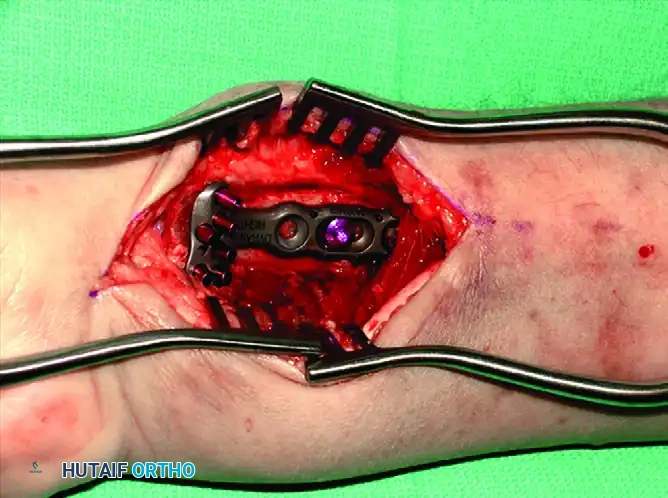

Recognizing the biomechanical pitfalls of isolated Kirschner wire fixation and standard plate-and-screw constructs—especially when dealing with highly comminuted intra-articular fractures in osteopenic bone—Medoff developed a comprehensive wrist fixation system. This system (commercialized as the TriMed system) combines the principles of pinning and plating to achieve stable, fragment-specific reconstruction of the distal radius.

Thin metaphyseal cortical bone does not hold standard screws well. Furthermore, conventional thick plates cannot be applied easily to the dorsal aspect of the distal radius due to the high risk of extensor tendon irritation and eventual rupture. Fragment-specific fixation utilizes low-profile wire-forms and pin-plates to capture these specific fragments without adding excessive bulk.

Fragment-Specific Implants and Application

1. The Radial Pin-Plate:

Applied to the radial column, this implant enhances stability by providing a radial buttress. It effectively neutralizes bending forces that would otherwise cause the radial styloid to displace proximally and radially.

Associated Surgical & Radiographic Imaging